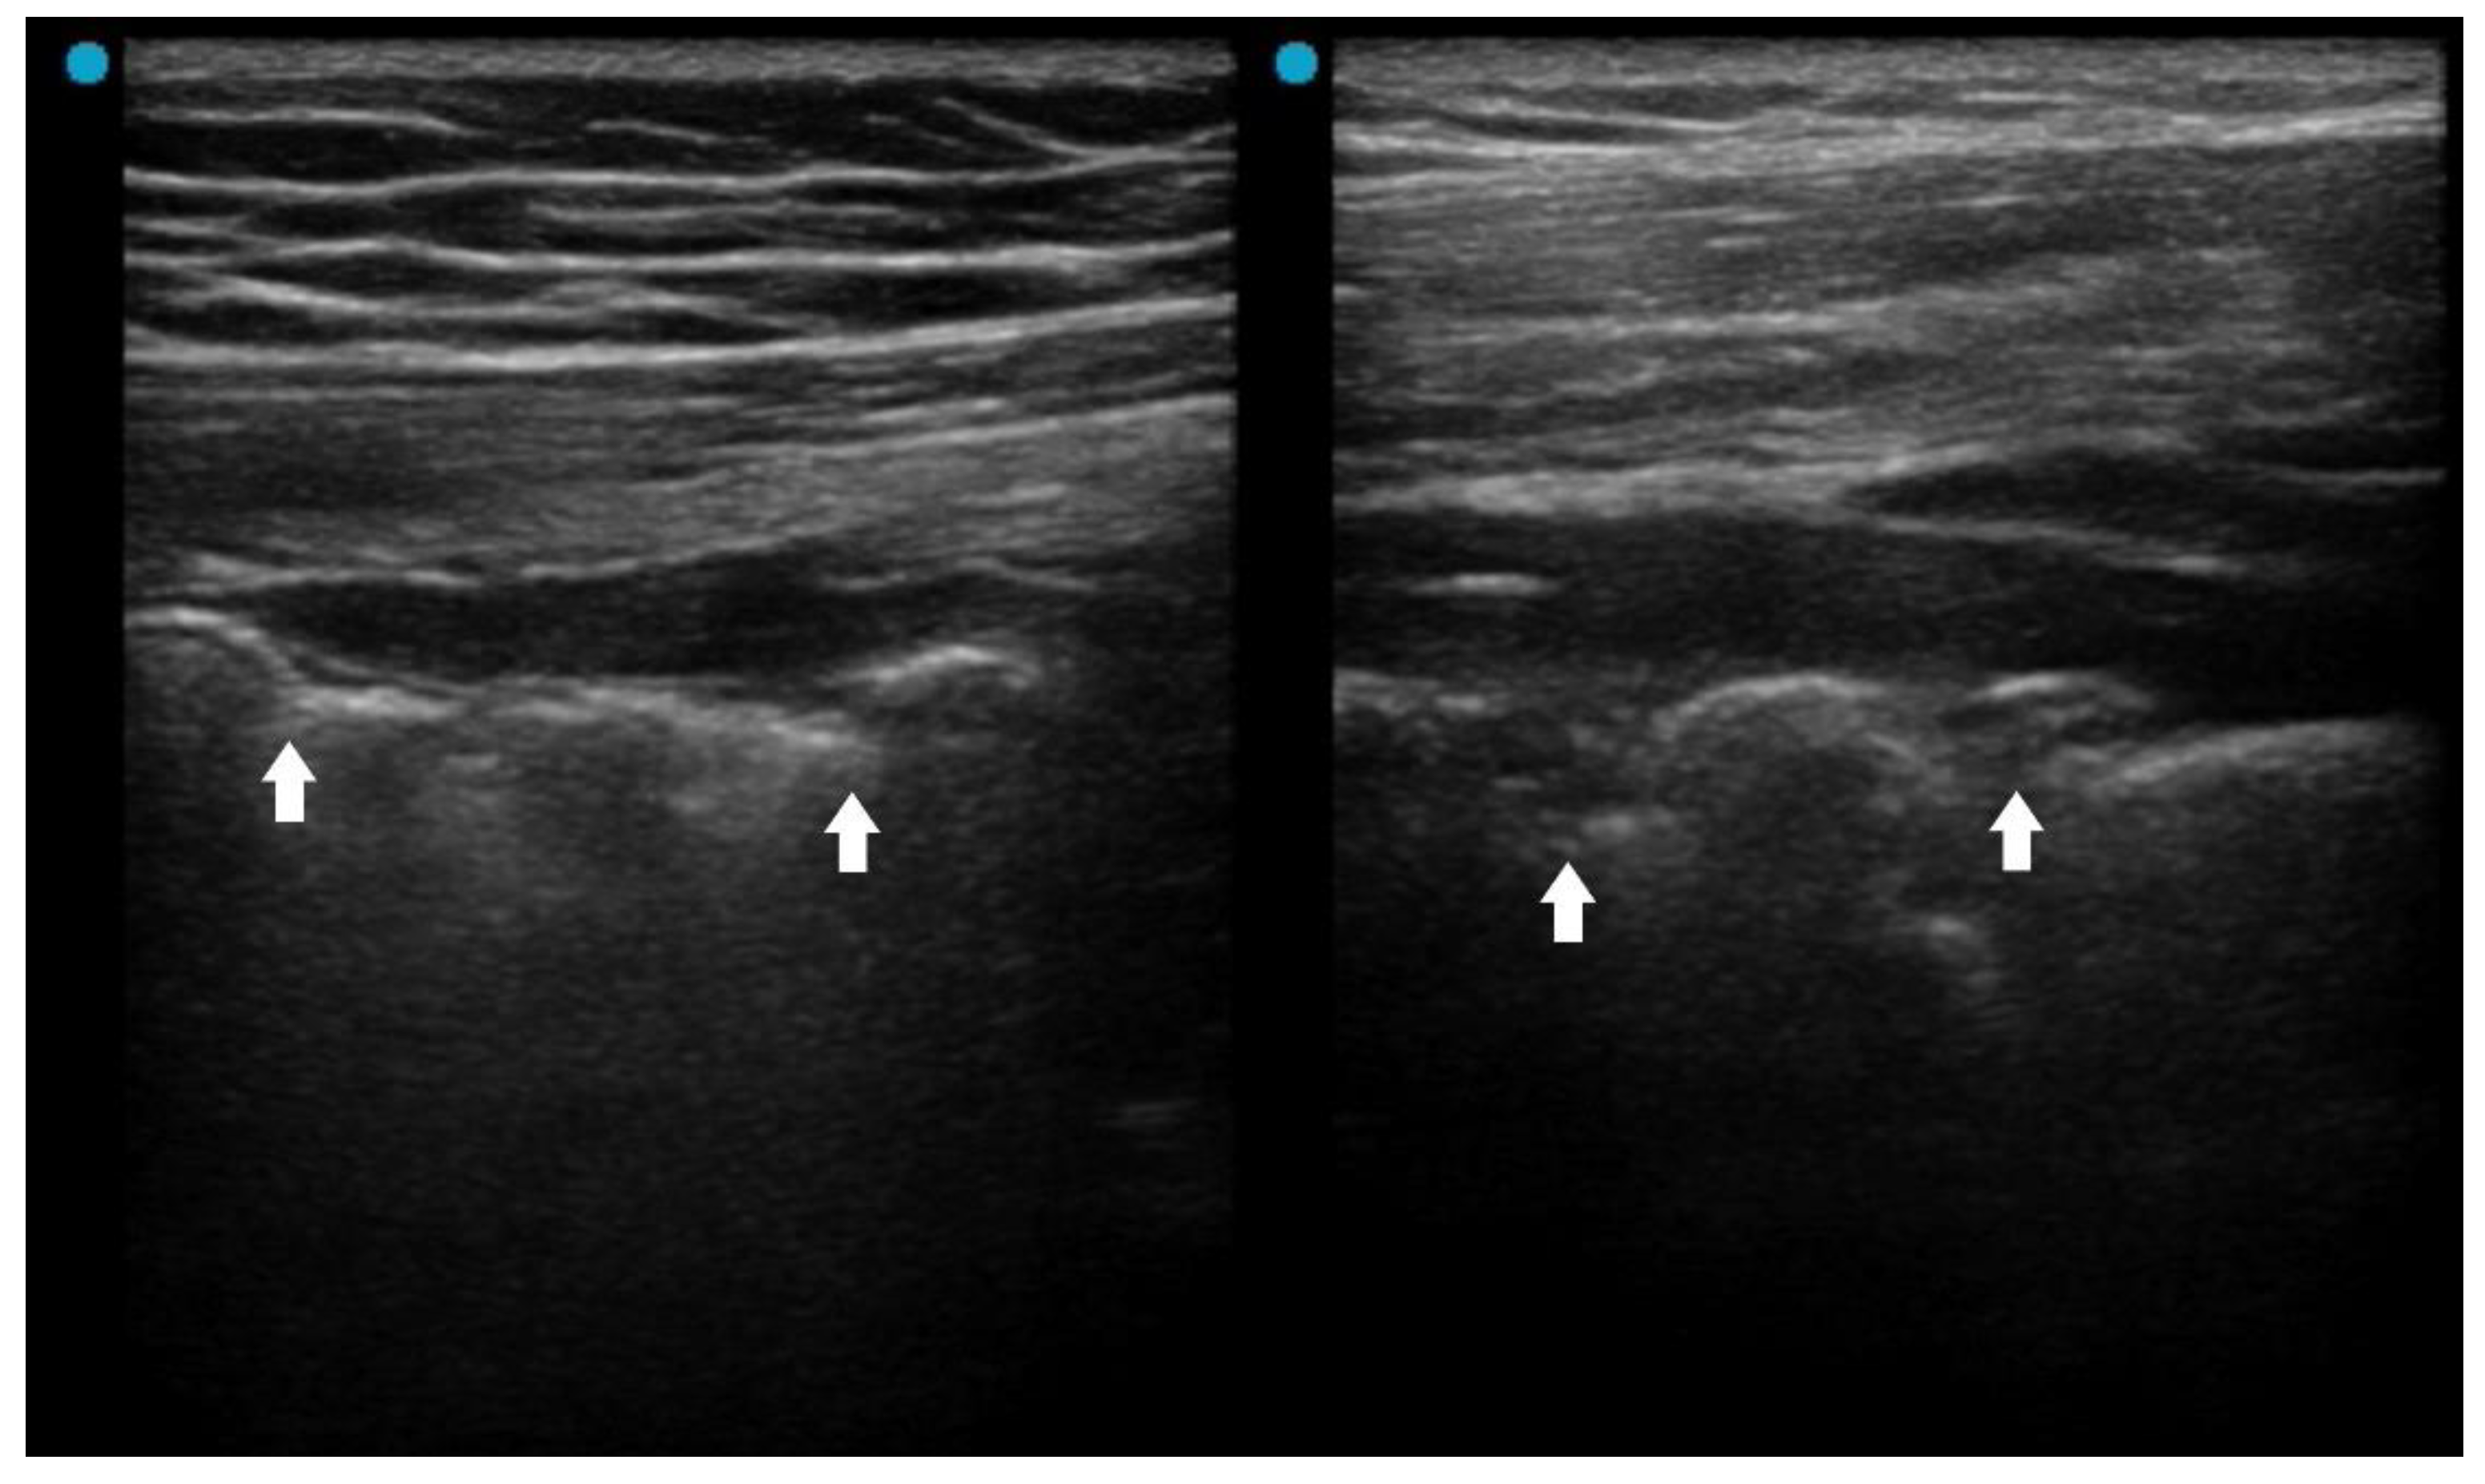

Fluid bronchogram is originally described as a sign on CT [23]. It is also described in post-obstructive pneumonia in ultrasonography, identified as anechoic tubular structures with hyperechoic walls but without color Doppler signals (Figure 2) [24,25].

Post-obstructive pneumonia with a fluid bronchogram usually reflects complete bronchial obstruction, making the consolidation refractory to antibiotic therapy alone.

The ultrasonographic appearance of pneumonia in children can be used for adults [22]. A study investigated pediatric hospitalized patients found that children with a uncomplicated CAP presented an air, arboriform, superficial and dynamic bronchogram, as opposed to complicated CAP which had an air and liquid bronchogram, deep, fixed [26]. Another pediatric study reported that fluid bronchogram, multifocal involvement, and pleural effusion were associated with adverse outcomes, including longer hospital stay, ICU admission, and tube thoracotomy in hospitalized CAP children [27].

Figure 2. Fluid bronchogram (arrows) in a patient with left upper lobe obstructive pneumonia.